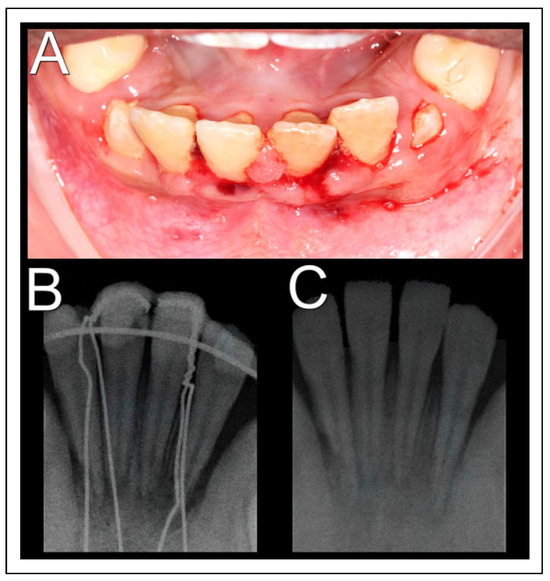

In second intervention, the use of titanium mini screws was not feasible due to the thin alveolar bone wall, as the stabilization of the screws could not be achieved, in addition to the risk of damage to dental germs. So, another treatment modality was chosen. Up with a new dental splinting, proceeded with a circummandibular cerclage using steel wire number 1, encompassing the base of mandible and the alveolar segment, bilaterally, between teeth 31 and 32 and between 41 and 42 (Figure 2A and B). In the immediate postoperative radiographic examination, a satisfactory fracture reduction and cerclage positioning were observed (Figure 2C and D). With this technique, greater stability of the dentoalveolar fragment and occlusion was achieved, allowing the local healing process. The patient received postoperative recommendations, mainly to maintain a soft diet.

Figure 2. Surgical procedure. (A) Transoperative photograph showing dentoalveolar segment stabilization by a circummandibular wire associated with a new dental splint; (B) intraoral photography in immediate postoperative period; (C) postoperative skull radiography in lateral position; (D) postoperative skull radiograph in posteroanterior position.

Figure 3. Ninety-day follow-up. (A) Intraoral image after removal of steel wires and dental splint; (B) periapical radiography of lower incisors prior to circummandibular wires removal; (C) periapical radiography after removing the steel wires.